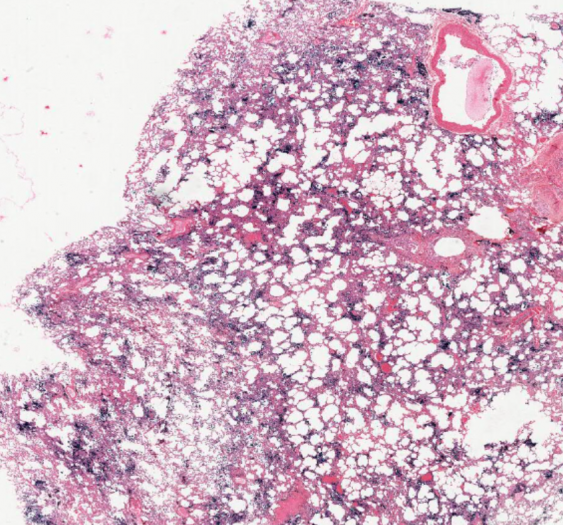

细胞和组织的适应与损伤

心源性肺含铁血黄素沉着症(铁染色)及炭末沉着症